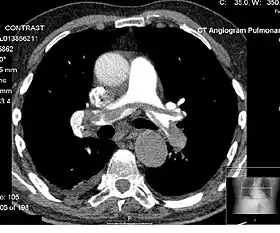

Angiography

Computed tomography angiography (CTA) is a type of contrast CT to visualize the arteries and veins throughout the body.[47] This ranges from arteries serving the brain to those bringing blood to the lungs, kidneys, arms and legs. An example of this type of exam is CT pulmonary angiogram (CTPA) used to diagnose pulmonary embolism (PE). It employs computed tomography and an iodine-based contrast agent to obtain an image of the pulmonary arteries.[48][49][50] CT scans can reduce the risk of angiography by providing clinicians with more information about the positioning and number of clots prior to the procedure.[51][52]